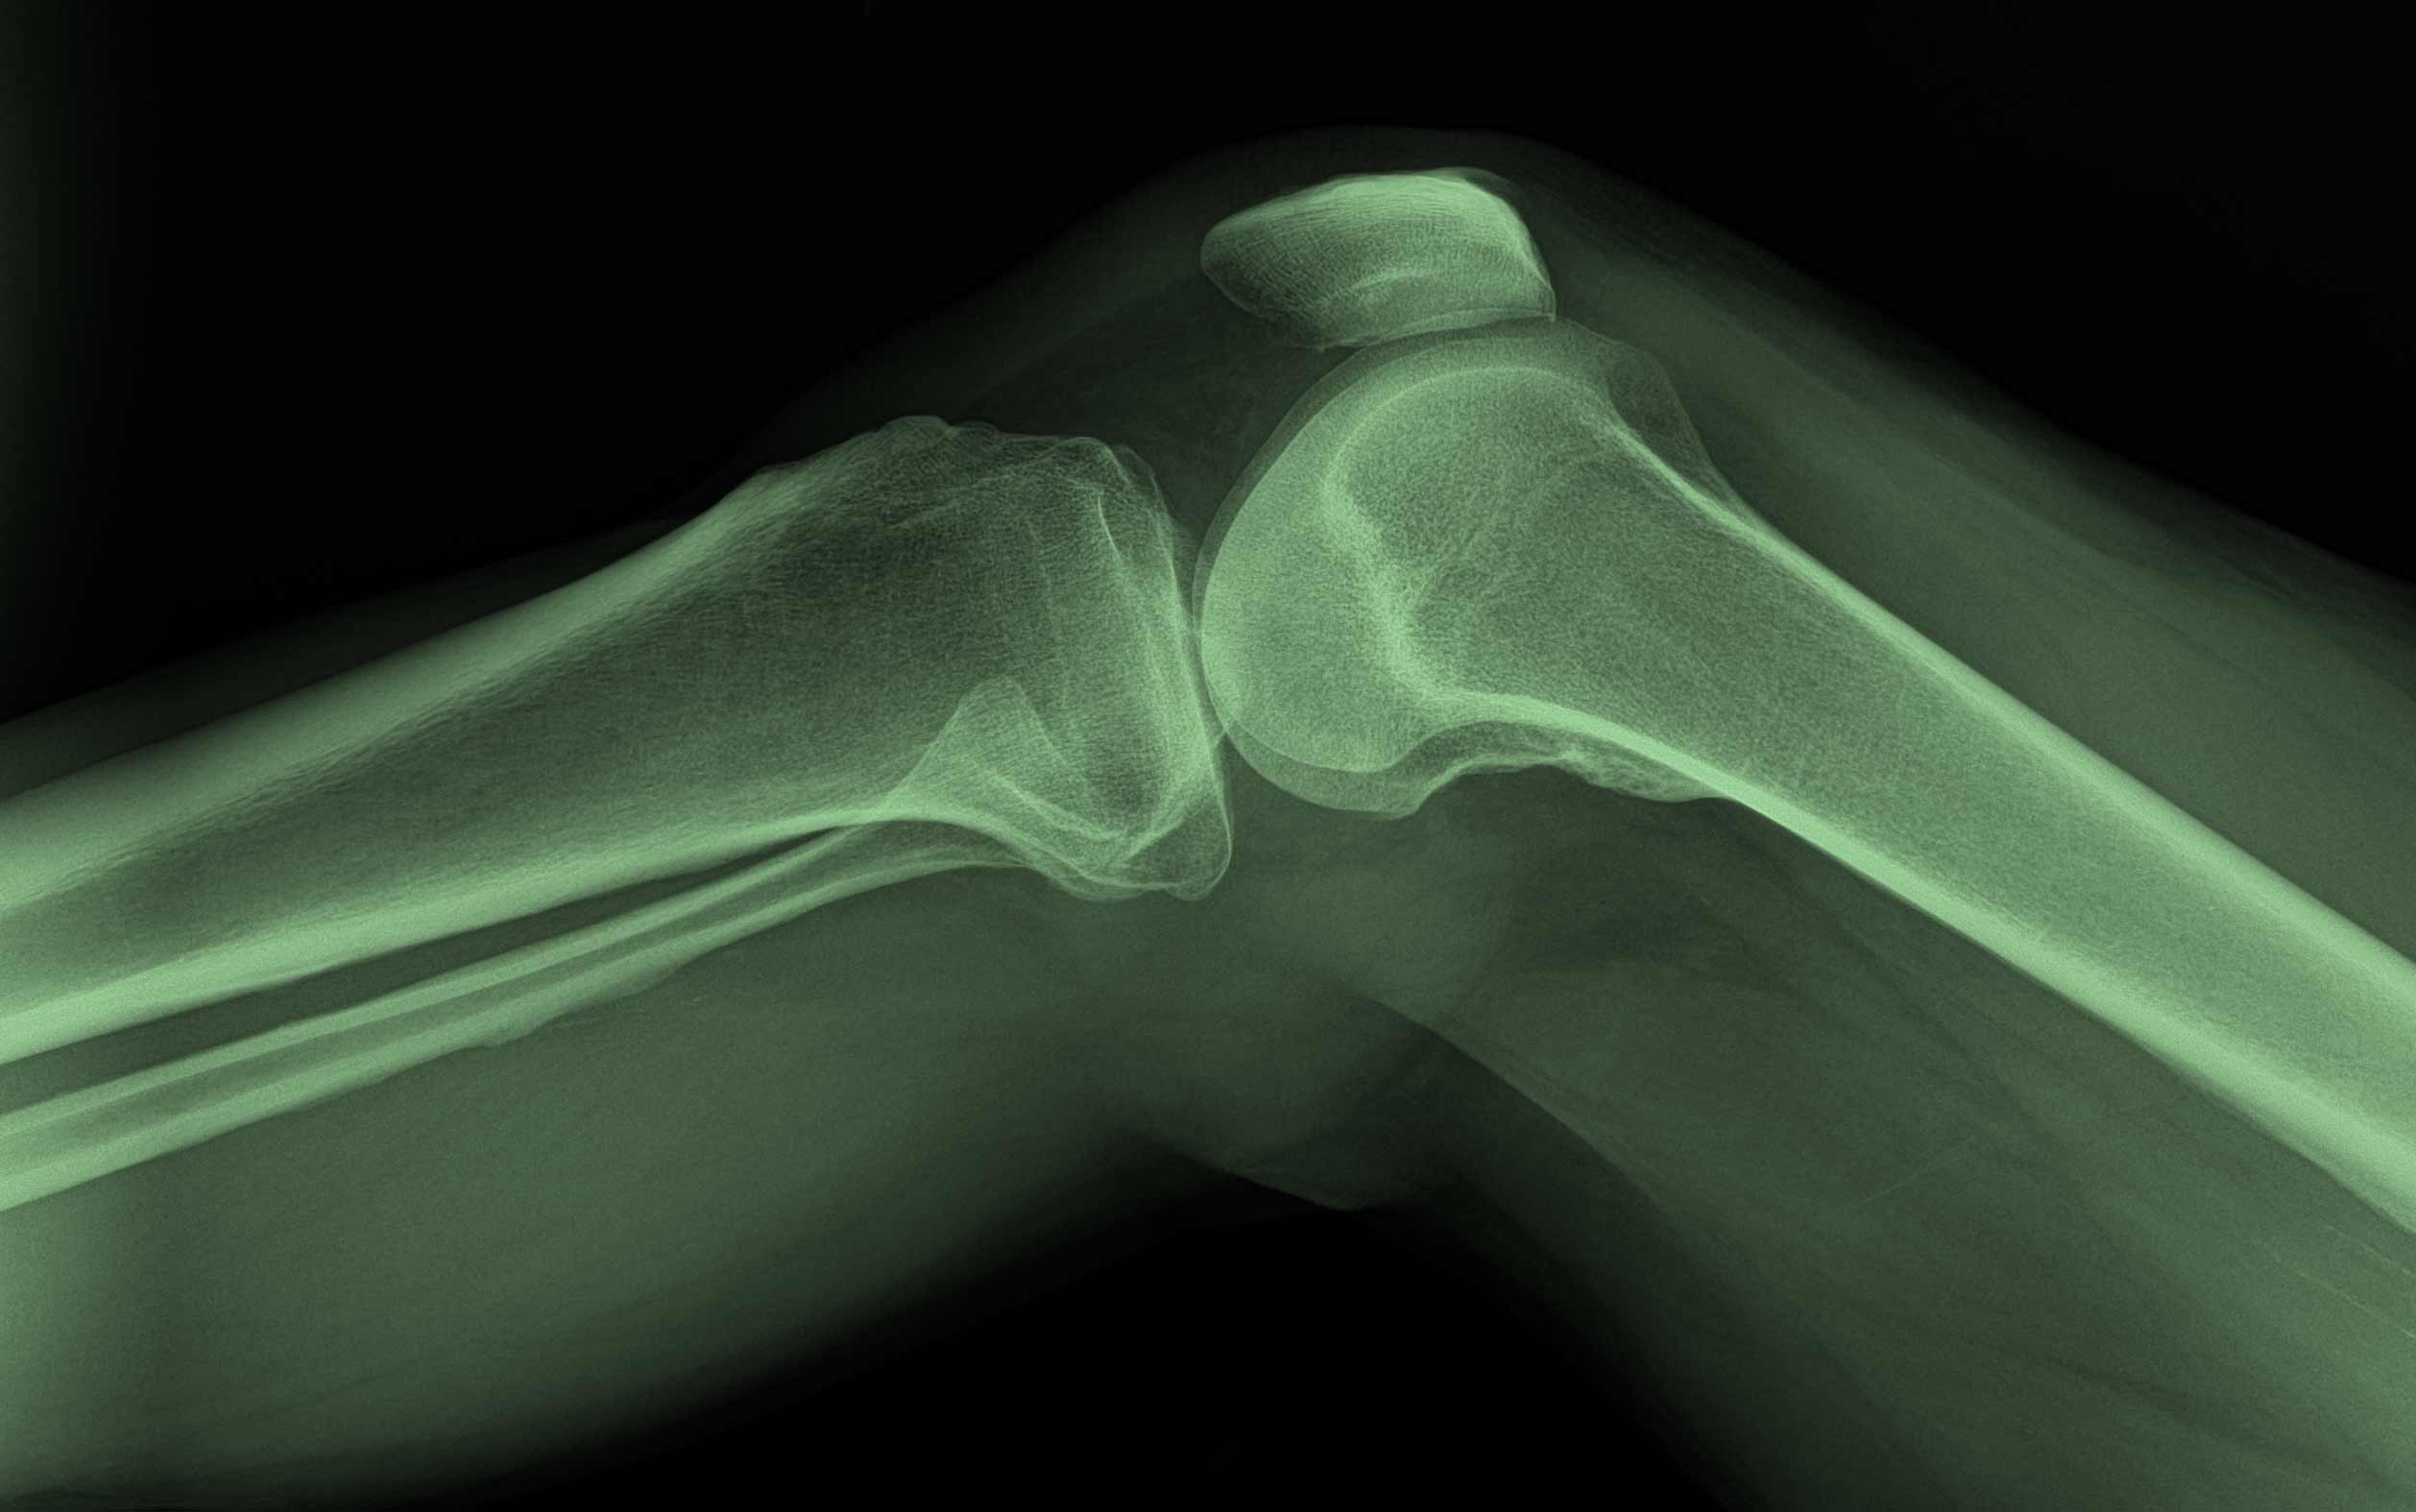

Fra mottagelsen ble pasienten sendt på røntgen og innlagt for videre undersøkelser. Det fantes ikke MR på denne tiden, så røntgenbilder var fasiten vi måtte leve med. Disse kunne stort sett bare bekrefte eller avkrefte brudd.

Diagnosene satt løst, og det var enighet om at «damen i 2-sengen» overdrev plagene sine. Det var jo ikke noe skadefunn på røntgenbildene. Men har man noen gang kunnet se smerte på røntgenbilder?

Årene har vist meg hvor lite vi egentlig kunne om noe så vanlig som en kneskade. Dette er ikke en historie fra steinalderen. Det var riktig nok i forrige århundre, men det skjedde i min egen yrkeskarriere. Brudd og meniskskader var nesten det eneste vi kjente til av skader i et kne. Dette var vanlig hos fotballspillere, og meniskene ble på 1970-tallet fjernet som blindtarmer. Det var store snitt, åpen kirurgi, og menisken ble klippet løs og tatt vekk. At dette 10–15 år senere skulle gi store slitasjeskader i leddbrusken, var det ingen som ofret en tanke. Som fotballspiller fikk man heller skryt for å være kjapt tilbake i kamp etter en vellykket meniskoperasjon.